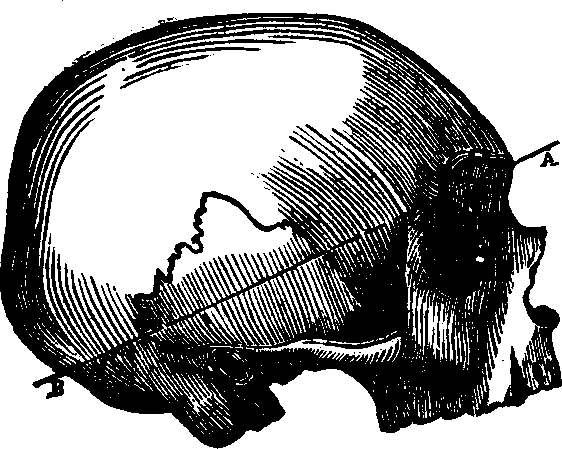

Fig. 10. The bones of the skull separated. 1. Frontal,

only half is seen. 2. Parietal. 3. Occipital, only half is

seen. 4. Temporal. 5. Nasal. 6. Malar. 7.

Superior maxillary (upper jaw). 8. Lachrymal. 9. Inferior

maxillary (lower jaw). Between 4 and 6 a part of the sphenoid

or wedge-shaped bone, is seen. Another bone assisting to form the skull,

but not here seen, is called the ethmoid (sieve-like, from being

full of holes), and is situated between the sockets of the eyes, forming

the roof of the nose.

The Bones of the Head are classed as follows: eight belonging to

the Cranium, and fourteen to the Face. The bones of the Cranium are the

occipital, two parietal, two temporal, frontal,

sphenoid, and ethmoid. Those composing the face are, the two

nasal, two superior maxillary, two lachrymal, two

malar two palate, two inferior turbinated, vomer, and

inferior maxillary. The cranial bones are composed of two dense

plates, between which there is, in most places a cancellated or cellular

tissue. The external [pg 23]plate is fibrous, the internal, compact and

vitreous. The skull is nearly oval in form, convex externally, the bone

being much thicker at the base than elsewhere, and it is, in every respect

admirably adapted to resist any injury to which it may be exposed, thus

affording ample protection to the brain substance which it envelops. The

internal surface of the cranium presents eminences and depressions for

lodging the convolutions of the brain, and numerous furrows for the

ramifications of the blood-vessels. The bones of the cranium are united to

one another by ragged edges called sutures, which are quite distinct

in the child but which in old age are nearly effaced. Some authorities

suppose that by this arrangement the cranium is less liable to be fractured

by blows; others think that the sutures allow the growth of these bones,

which takes place by a gradual osseous enlargement at the margins. The

bones of the Face are joined at the lower part and in front of the

cranium, and serve for the attachment of powerful muscles which assist in

the process of mastication. Although the soft parts of the face cover the

bony structure, yet they do not conceal its principal features, or

materially change its proportions. The form of the head and face presents

some remarkable dissimilarities in different races.